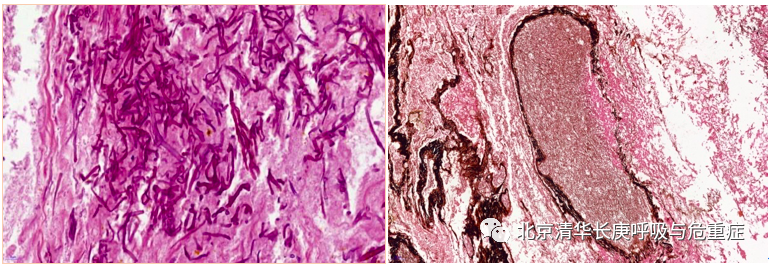

入院后行气管镜检查,并且应用导航和超声等精准定位技术,于右上叶前段、右下叶内基底段行病理活检:病理可见坏死组织内大量毛霉菌菌丝,并可见菌丝侵袭血管(图3)。支气管肺泡灌洗液及脓栓二代基因测序(mNGS)显示为微小根毛霉。最终确定诊断为急性髓系白血病合并肺毛霉菌病。

图3病理显示坏死组织内大量毛霉菌菌丝,并可见菌丝侵袭血管(GMS染色及弹力纤维染色)